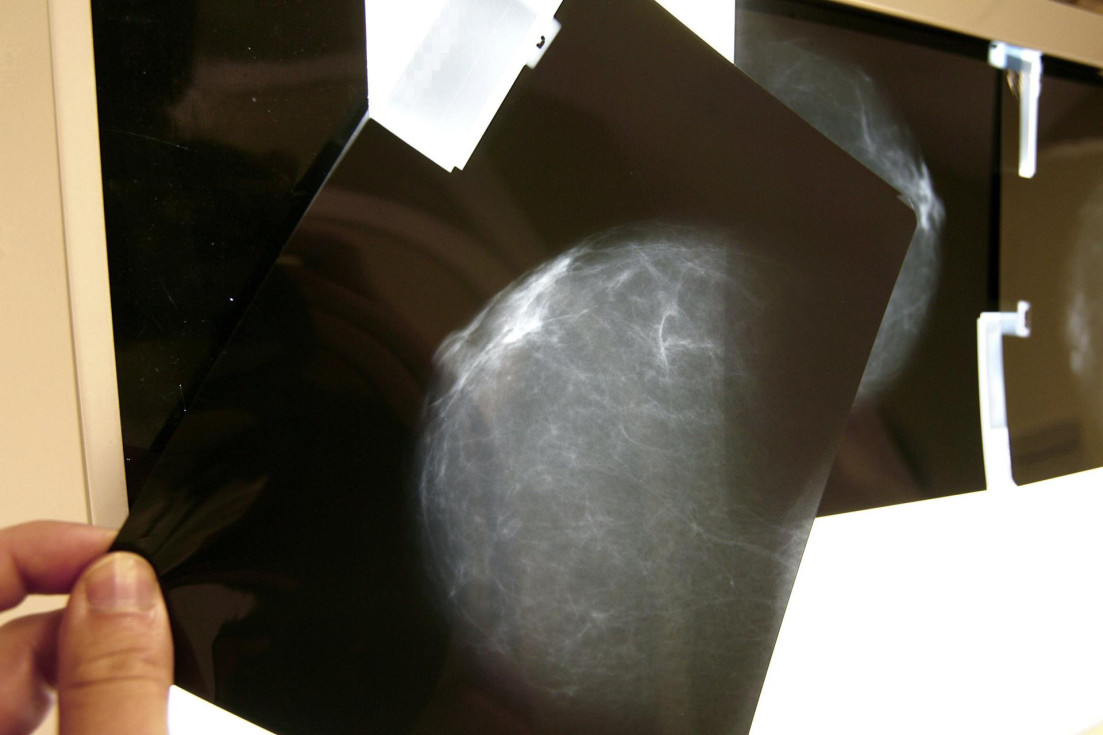

Fotografía de una prueba radiológica de mama. Imagen de archivo: EFE/Chema Moya

Las autoridades sanitarias valencianas recuerdan que el cribado mediante mamografía sigue siendo la herramienta más eficaz para detectar el cáncer de mama en sus fases iniciales. El programa autonómico, dirigido a mujeres de entre 45 y 69 años, invita cada dos años a realizar esta prueba de manera gratuita.